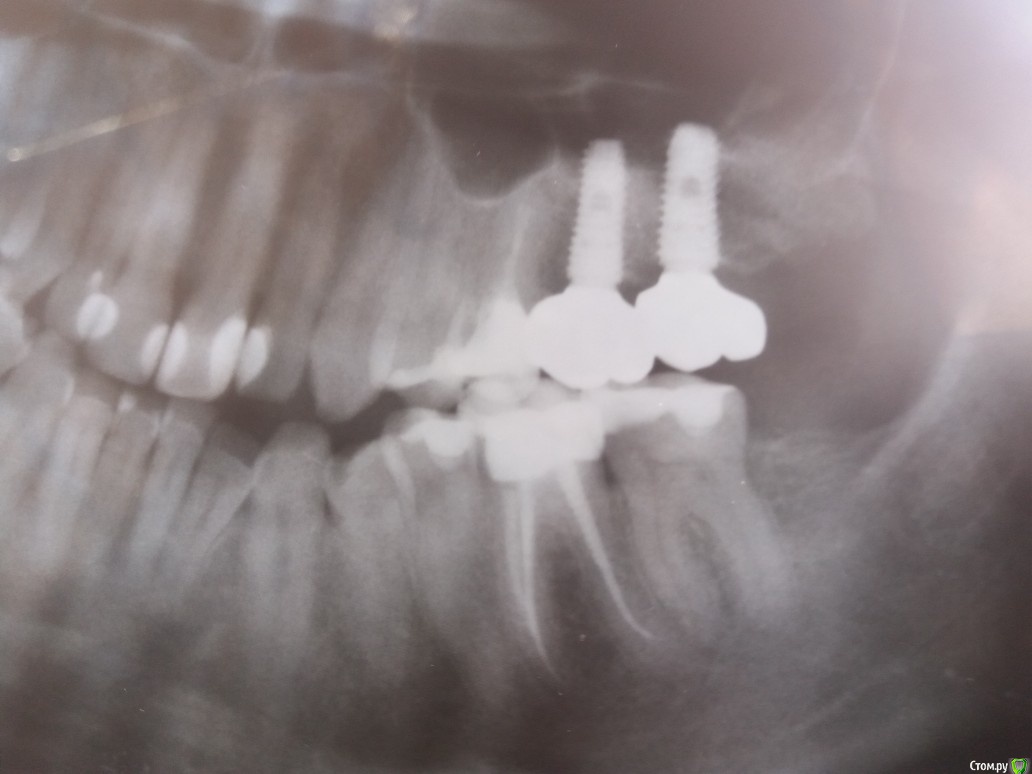

kuznetsovaev Опубликовано 19 июля, 2019 Автор Поделиться Опубликовано 19 июля, 2019 Это левая сторона Ссылка на комментарий